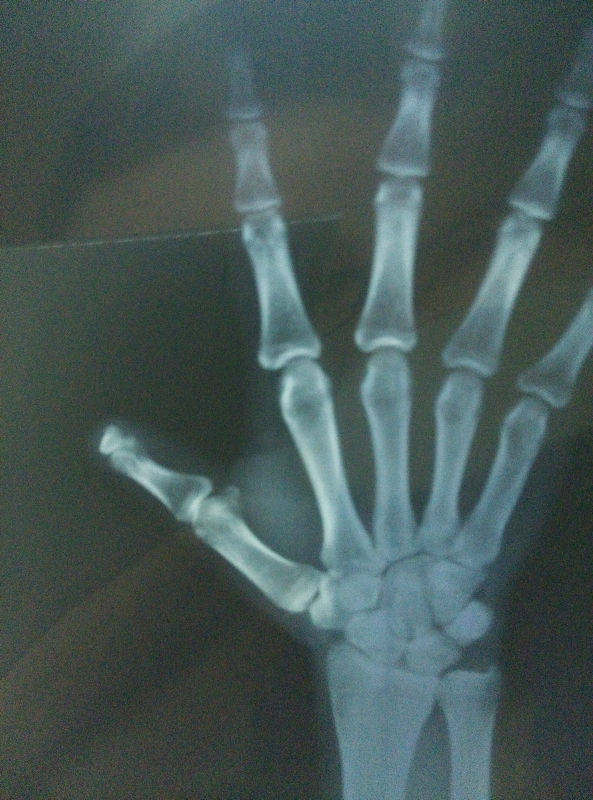

池老师,以下这个做再造效果怎么样呢

IMG_20150929_211059.jpg

IMG_20150929_211002.jpg